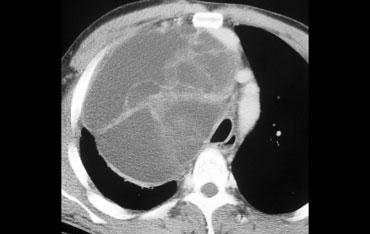

Hãy mô tả hình ảnh bên trái.

Sau đó tiếp tục.

Có nhiều khối ở cả trung thất trước và trung thất giữa.

Giá trị tỷ trọng tương đương tỷ trọng nước.

Các dấu hiệu này gợi ý chẩn đoán hạch bạch huyết dạng nang ở bệnh nhân có bệnh lý di căn.